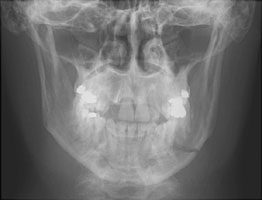

- Click on the image for a larger versionCAP radiograph of the mandible. This demonstrates bilateral fractures of the mandible.